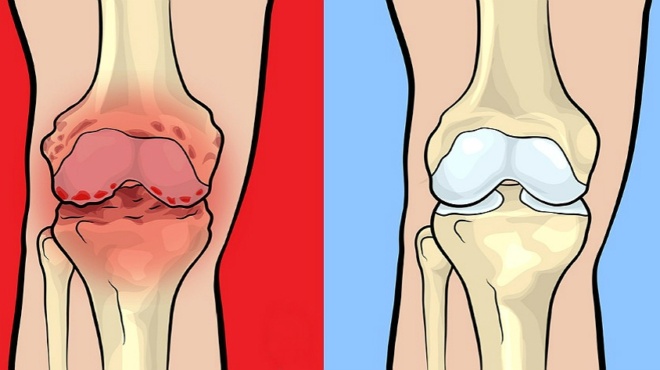

Οι αρθρικές επιφάνειες της κοτύλης και της κεφαλής του μηριαίου καλύπτονται από αρθρικό χόνδρο, μια λεία επιφάνεια που επιτρέπει την ομαλή ολίσθηση αλλά και την απορρόφηση των κραδασμών κατά τη διάρκεια της κίνησης και της φόρτισης.

Στις περισσότερες των περιπτώσεων ο πόνος και η δυσκαμψία στο ισχίο προκαλούνται από οστεοαρθρίτιδα. Η οστεοαρθρίτιδα και τυχόν άλλα προβλήματα της άρθρωσης του ισχίου μπορεί να διαγνωστούν με ειδικές εξετάσεις όπως η Αξονική ή η Μαγνητική τομογραφία. Ωστόσο, στη συνέχεια η αντιμετώπισή τους μπορεί να απαιτήσει μια αρθροσκόπηση ισχίου. Μία αρθροσκόπηση ισχίου επιτρέπει στο χειρουργό σας τη διάγνωση και τη θεραπεία κάποιων προβλημάτων που επηρεάζουν την άρθρωση του ισχίου σας, χωρίς την ανάγκη για μια μεγάλη τομή στο δέρμα και τους υποκείμενους ιστούς. Αυτή η διαδικασία μπορεί να μειώσει το ποσό του πόνου που αισθάνεστε και να επιταχύνει την αποκατάσταση σας μετά την επέμβαση.